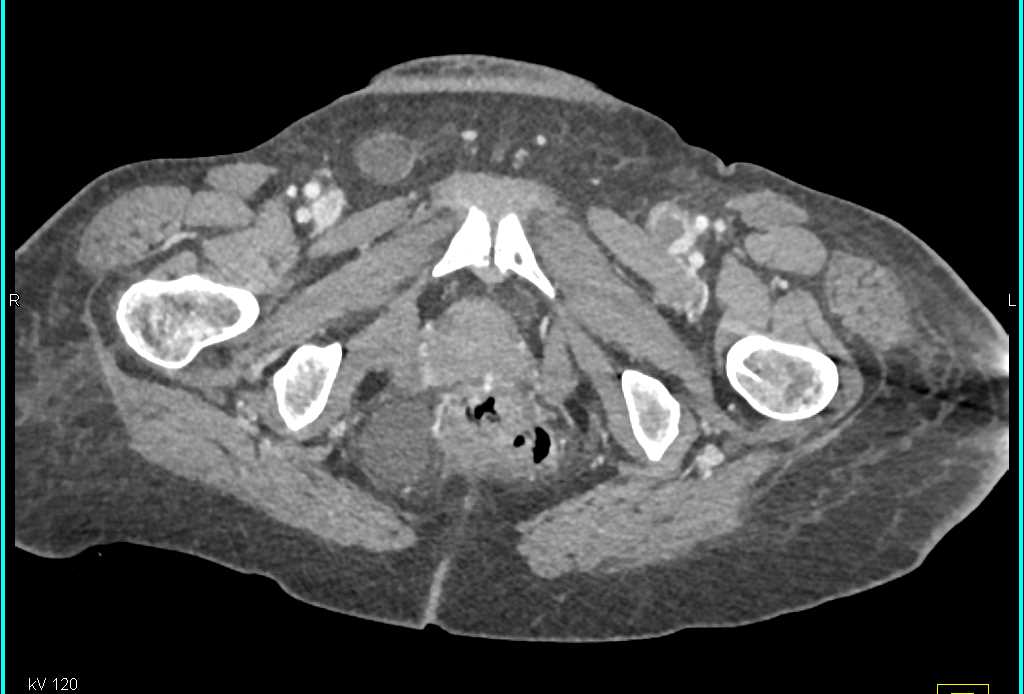

Diagnosis

CTA Circle of Willis